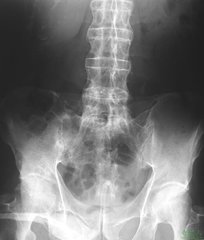

首先,我们来了解一下什么是强直性脊柱炎?强直性脊柱炎是不常见风湿免疫性疾病,是血清阴性关节病的一种,研究表明,该病原因尚不很明确,以脊柱为主要病变的慢性疾病,病变主要累及骶髂关节,引起脊柱强直和纤维化,造成弯腰、行走活动受限,并可有不同程度的眼、肺、肌肉、骨骼的病变,也有自身免疫功能的紊乱,所以又属自身免疫性疾病。

一般而言,强直性脊柱炎在临床上主要有如下几种表征:腰背痛、晨僵、腰椎各方向活动受限和胸廓活动度减低是强直性脊柱炎的典型表现,在病情活动期间表现更为明显。通常来说,强直性脊柱炎腰痛的症状不会因为休息而得到缓解,活动反而使症状减轻。活动期常有夜间痛,可影响睡眠,严重者可于入睡以后惊醒。大部分病历早上起床时觉腰背僵硬、活动不灵活,医学上将其称为“晨僵”,适当活动也可缓解。

据医生介绍,强直性脊柱炎和其他疾病一样,早期可以达到临床治疗的,治好后和正常人一样,到了中晚期脊柱骨桥形成,通过治疗只能达到疼痛症状消失,骨骼变形停止,病情不发展的程度,这就是医生说的临床治疗。强直性脊柱炎中晚期脊柱骨桥形成,根本不能通过治疗使骨桥消失达到早期那样的临床治疗效果。如果强直性脊柱炎中晚期患者治疗后,想达到骨质彻底治好,几率是很小的。